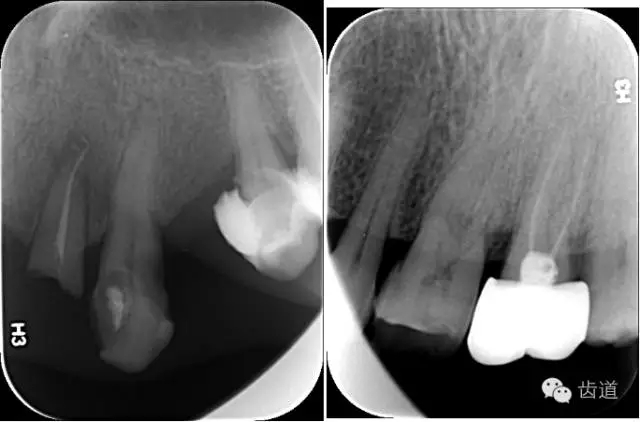

X線:根尖片、曲面斷層片(牙槽嵴頂,水平垂直吸收,程度)

21.webp.jpg

22.webp.jpg

23.webp.jpg